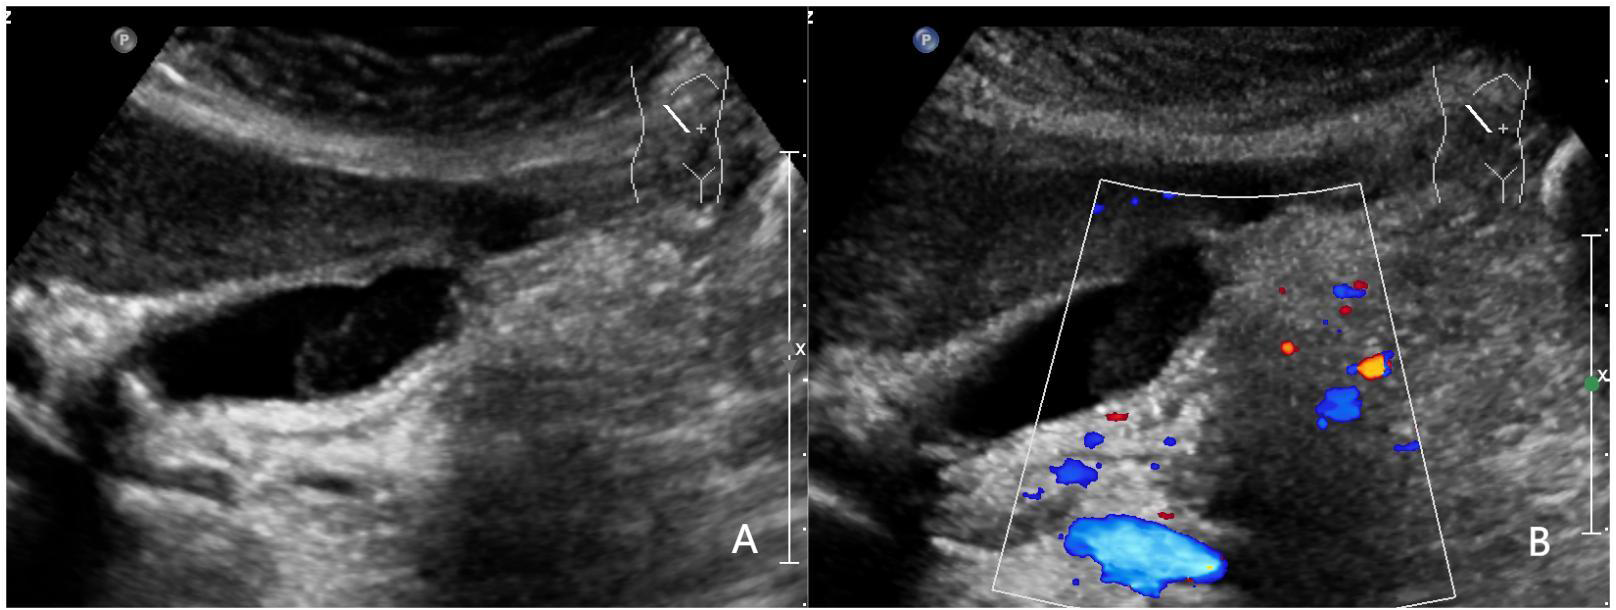

Figure 4

www.frontiersin.org

Figure 4 A 52-year-old woman with pathologically proven chronic cholecystitis. (A) Focal thickening of the base of the gallbladder, with no stratified appearance, and loss of interface with the liver.; (B) CDFI=0.Based on a consensus review of the sonographic findings, the lesion was categorized as GB-RADS 4, GB-RADS+CDFI 3.